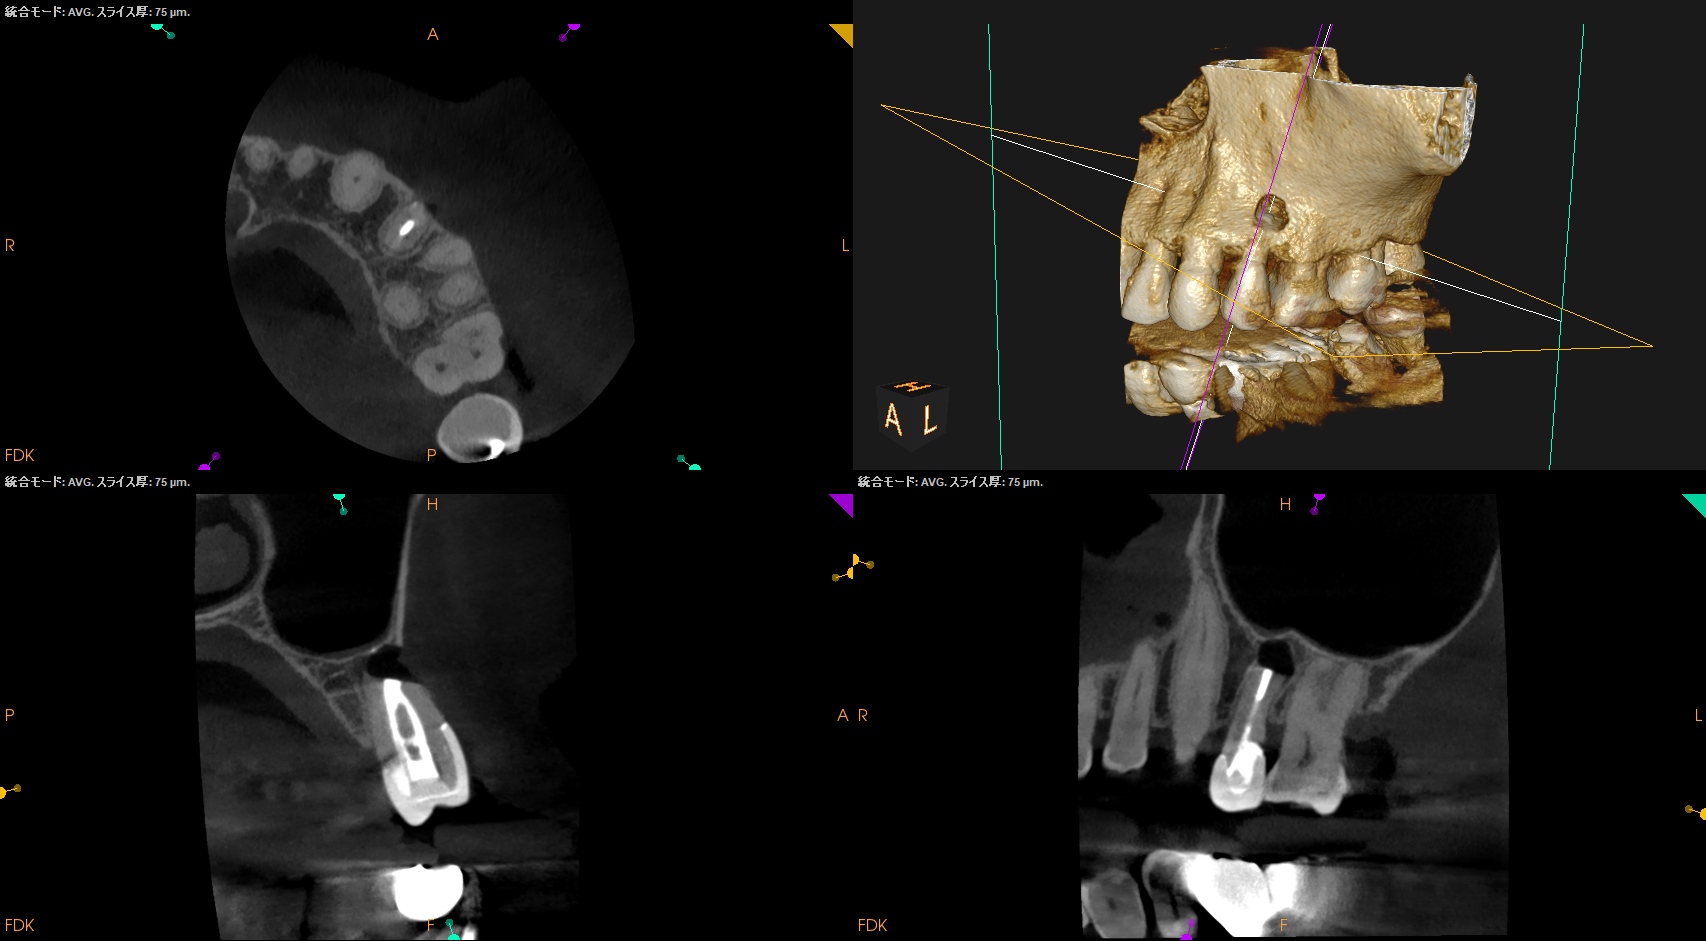

#13 Apicoectomy(2025.10.7)

思しき部位をOsteotomyした。

すると、Apexが顔を出したので3mm Root resectionした。

メチレンブルーで染色後にRetroprep, Retrofillした。

術後にPA, CBCTを撮影した。

問題はないだろう。